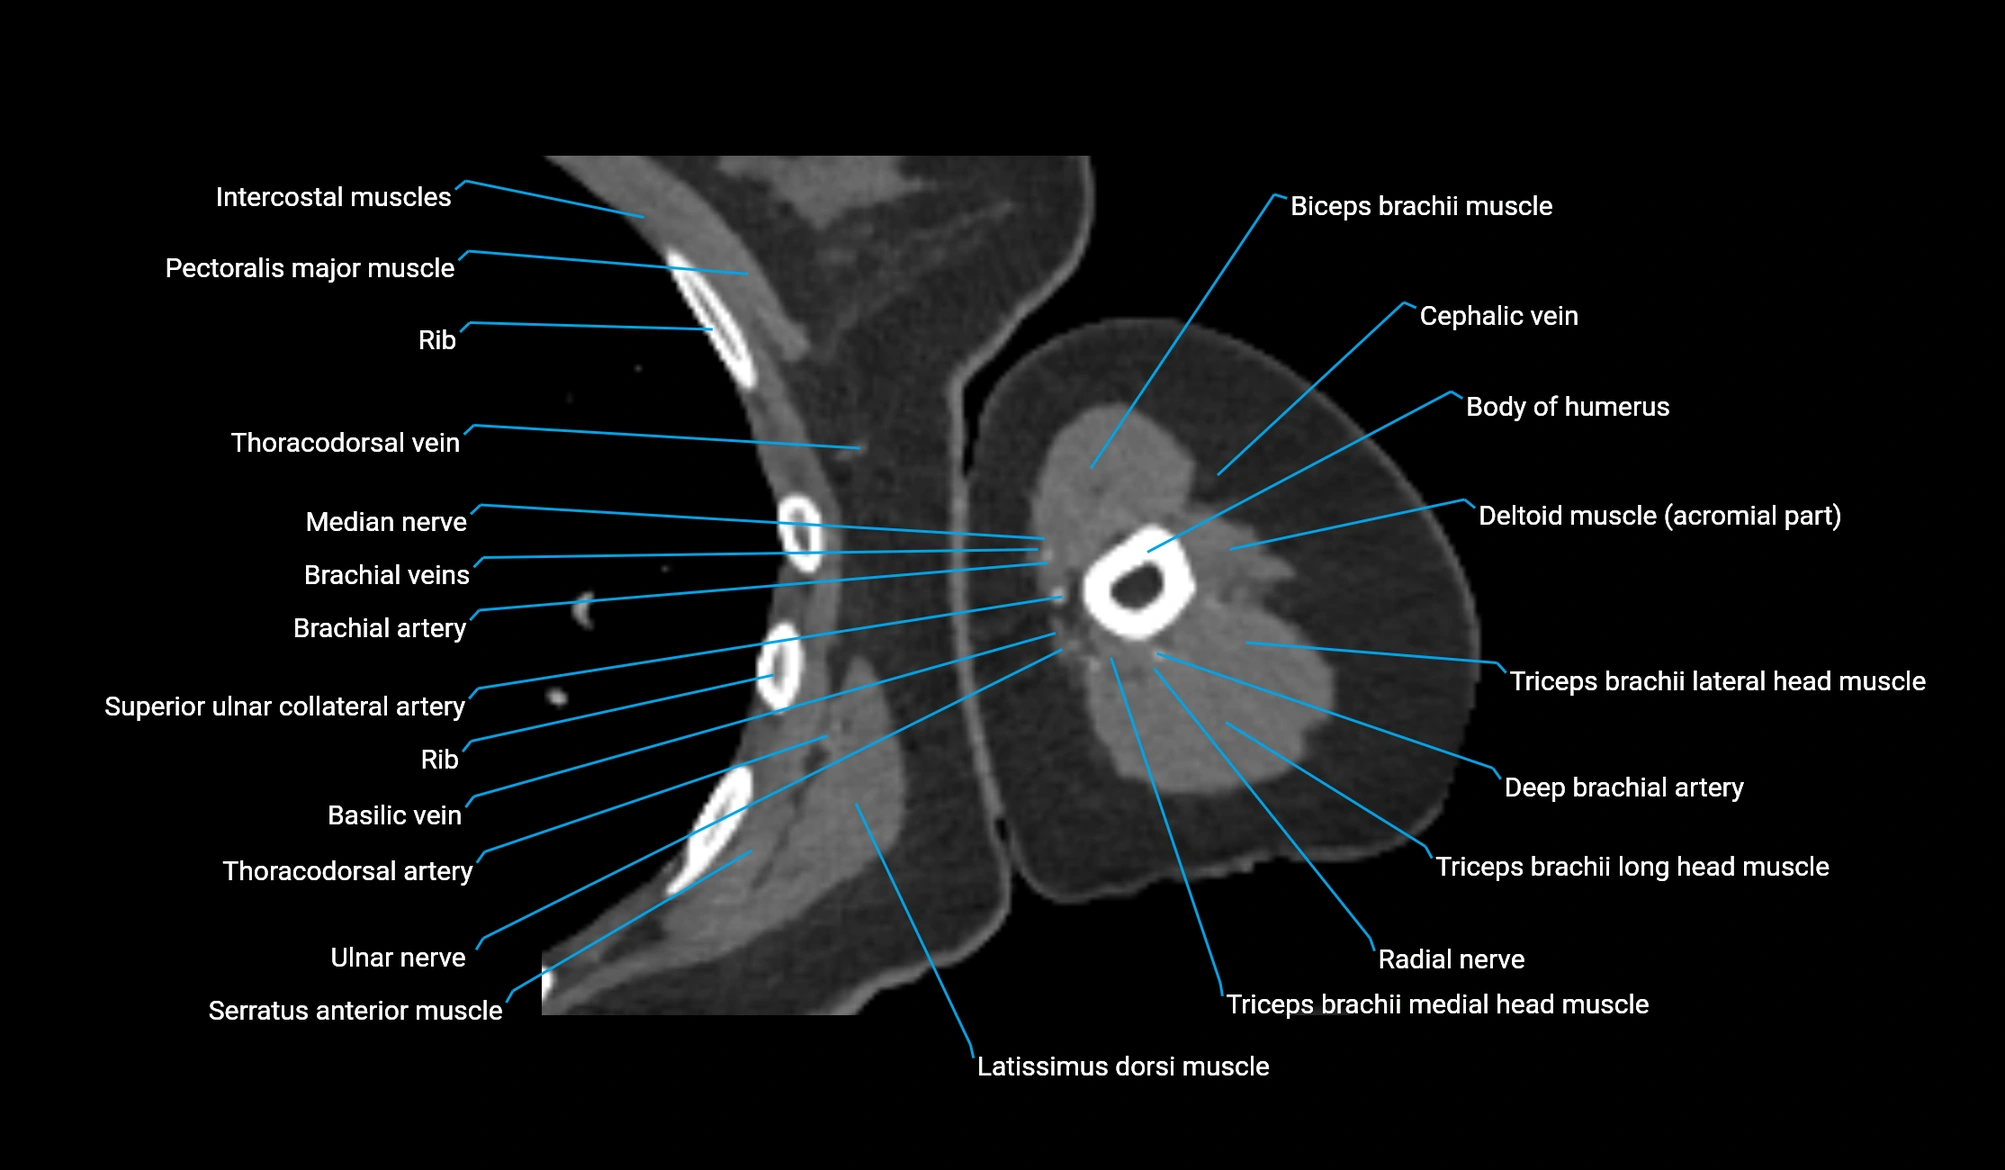

- Body of humerus

- Brachial artery

- Brachial fascia

- Cephalic vein

- Deep brachial artery

- Lateral head of triceps brachii muscle

- Long head of triceps brachii muscle

- Medial head of triceps brachii muscle

- Median nerve

- Radial nerve

- Superior ulnar collateral artery

- Thoracodorsal artery

- Ulnar nerve